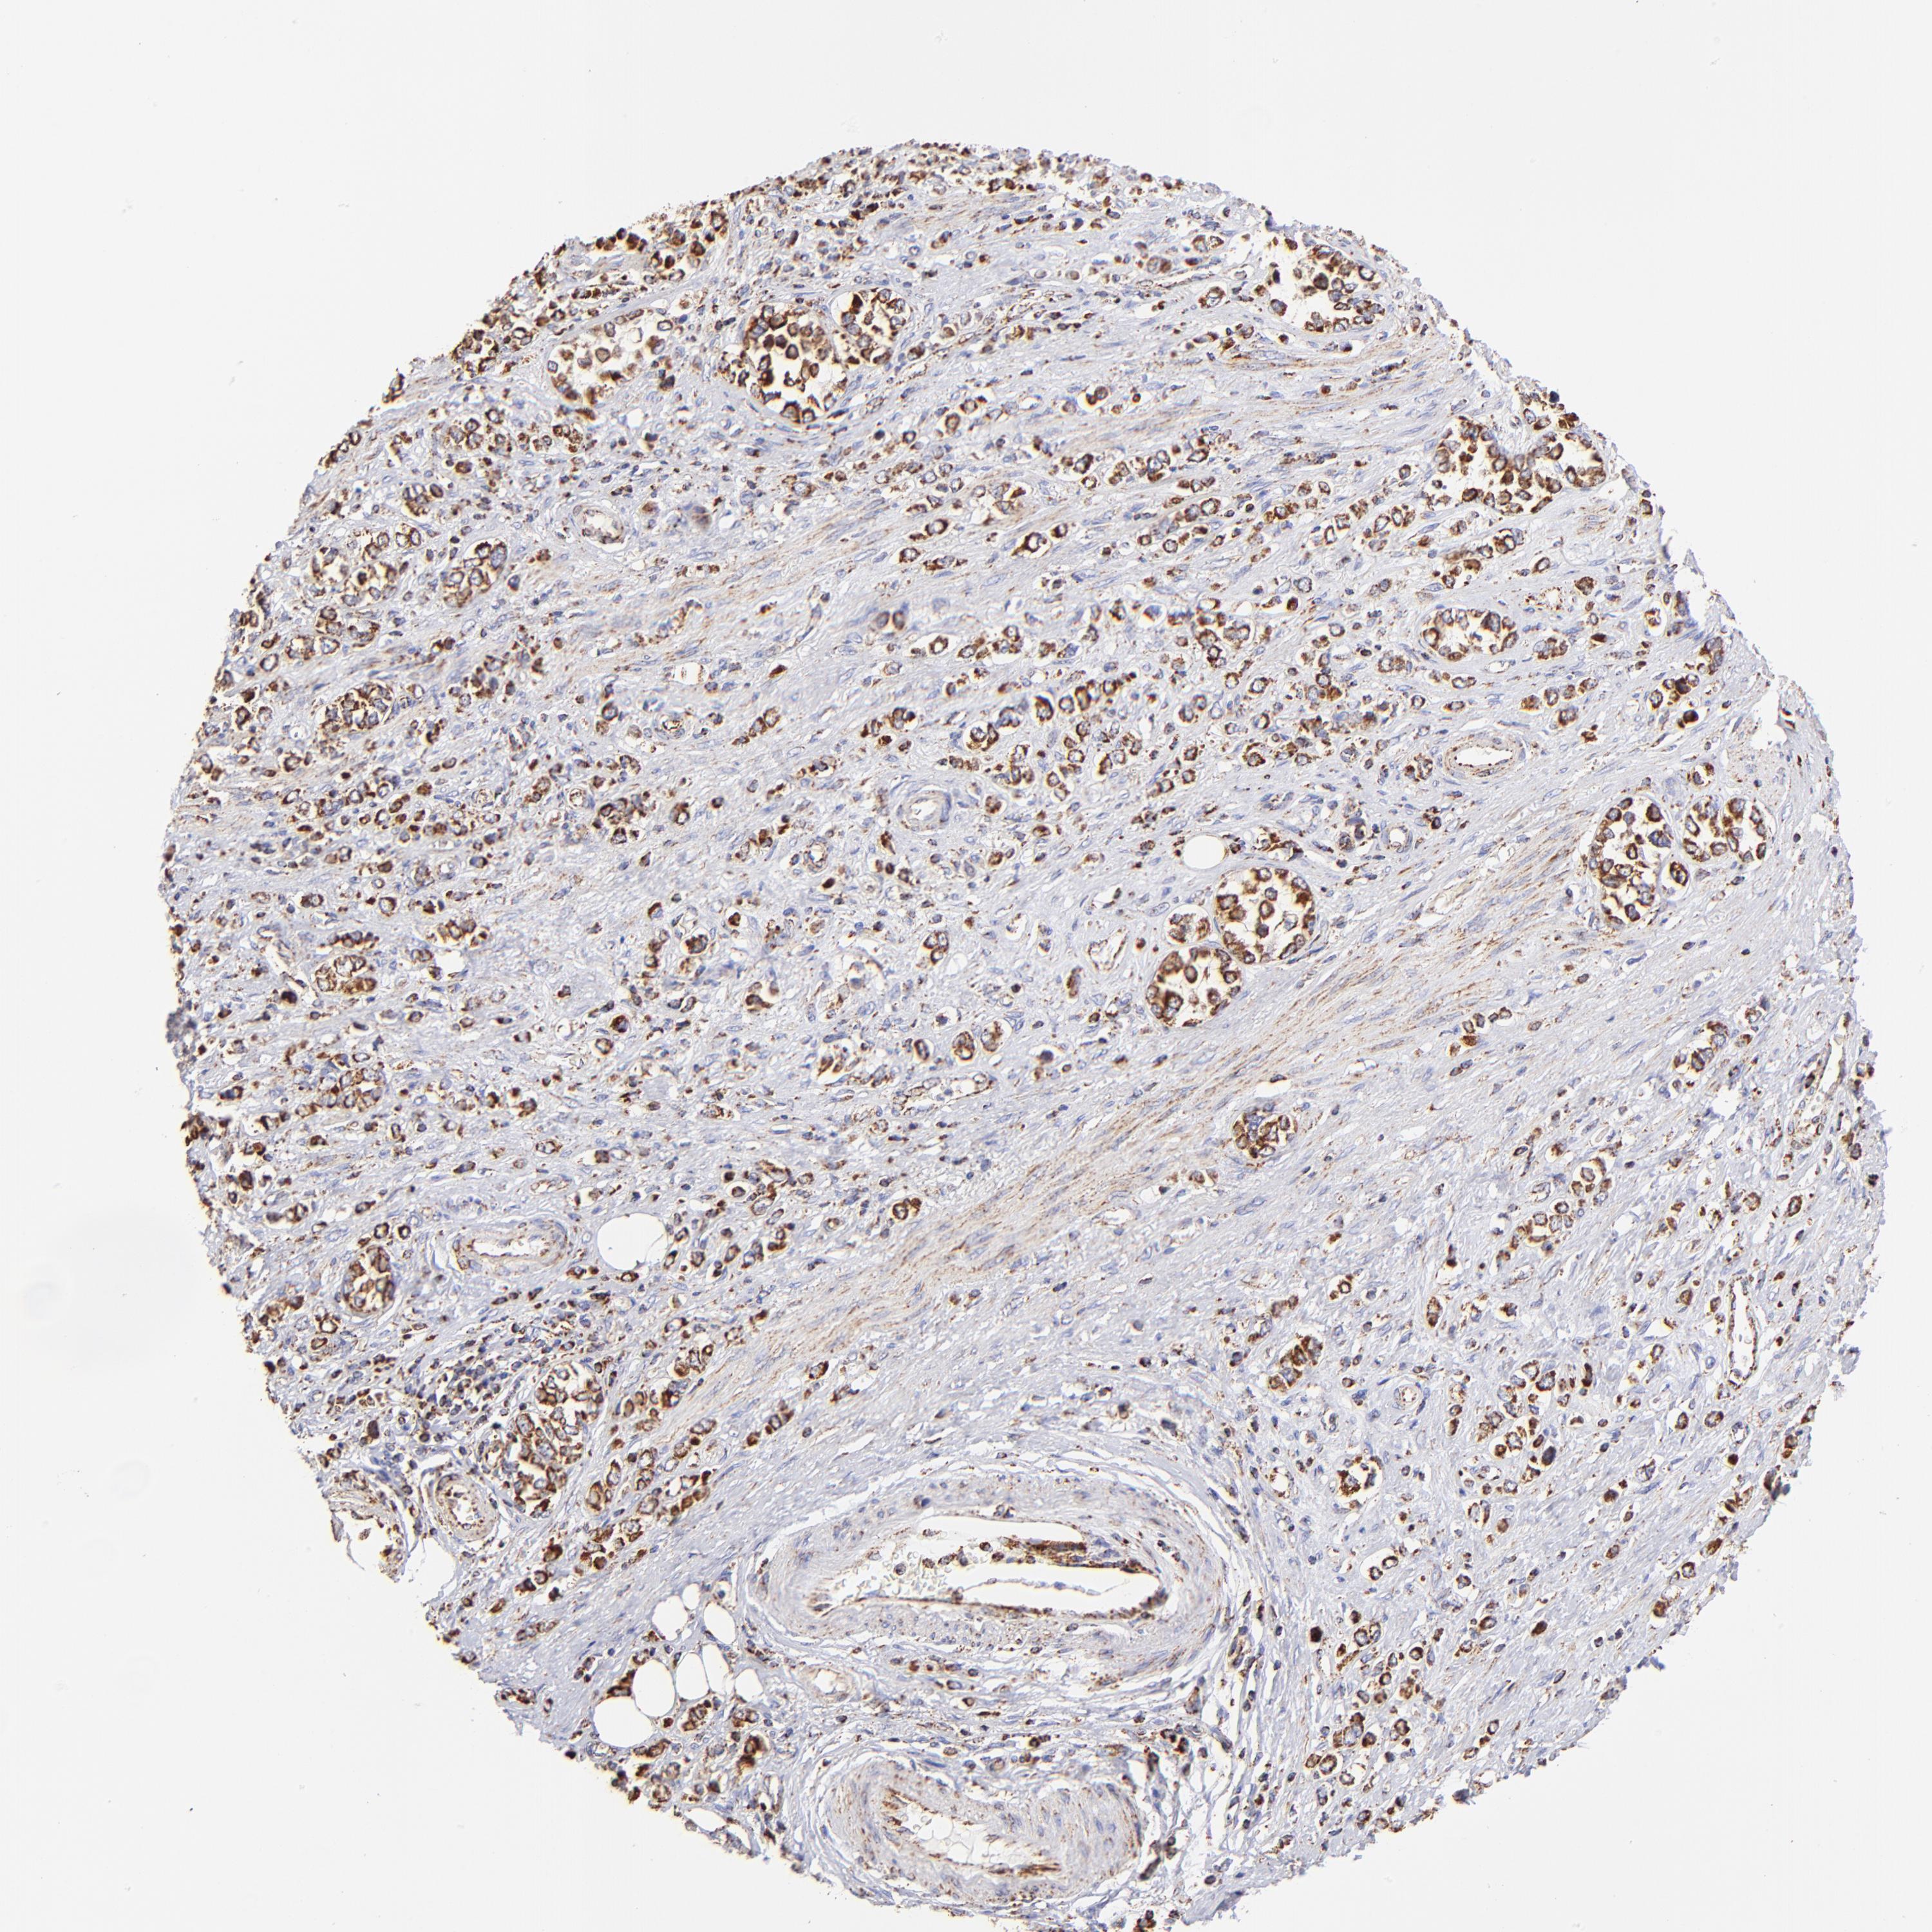

STOMACH CANCER - Protein expressioni

A mouse-over function shows sample information and annotation data. Click on an image to view it in a full screen mode. Samples can be filtered based on level of antibody staining by selecting one or several of the following categories: high, medium, low and not detected. The assay and annotation is described here.

Note that samples used for immunohistochemistry by the Human Protein Atlas do not correspond to samples in the TCGA dataset.

Antibody stainingi

Antibody staining in the annotated cell types in the current human tissue is reported as not detected, low, medium, or high, based on conventional immunohistochemistry profiling in selected tissues. This score is based on the combination of the staining intensity and fraction of stained cells.

Each image is clickable and will lead to virtual microscopy that enables deeper exploration of all samples and also displays staining intensity scores, fraction scores and subcellular localization as well as patient and tissue information for each sample.

Antibody HPA002907

Antibody HPA005835

Staining

High

Medium

Low

Not detected

Intensity

Strong

Moderate

Weak

Negative

Quantity

>75%

75%-25%

<25%

None

Location

Nuclear

Cytoplasmic/membranous

Cytoplasmic/membranous,nuclear

Adenocarcinoma, NOS

Adenocarcinoma, High grade